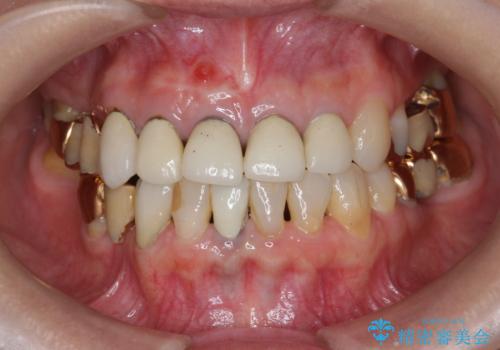

即切歯の抜歯を行う場合犬歯を含めたブリッジによる補綴計画を立てることが多いですが、今回は犬歯から大臼歯にかかる大きなブリッジが既に装着されていたため予算とご希望を相談し前歯のみの延長ブリッジ補綴で治療を行っていくこととしました。

- 54万円(仮歯・感染根管治療・ファイバーコア・ジルコニアクラウン×4) (税別)費用は治療当時の料金となります

歯列全体を治療の対象とする治療計画が予算や期間により難しい場合、状況に応じて最善の治療結果が出せるよう治療のゴールを相談しながら決定することが可能です。